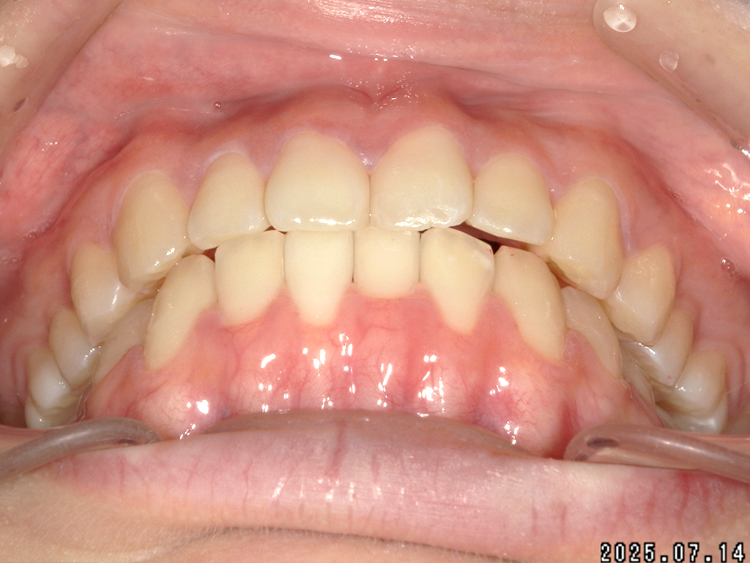

症例4

Before

After

| 主訴 | 上下前歯のがたつき |

| 年齢 | --- |

| 治療 期間 |

約9ヶ月 |

| 治療 内容 |

インビザラインiGoで上下顎の治療。 |

| 治療費 | ¥550,000(税込)/調整料含む |

| 治療のリスク | 矯正終了後は、リテーナーを指示通りに使用し、歯の後戻りを防ぐ必要があります。 |